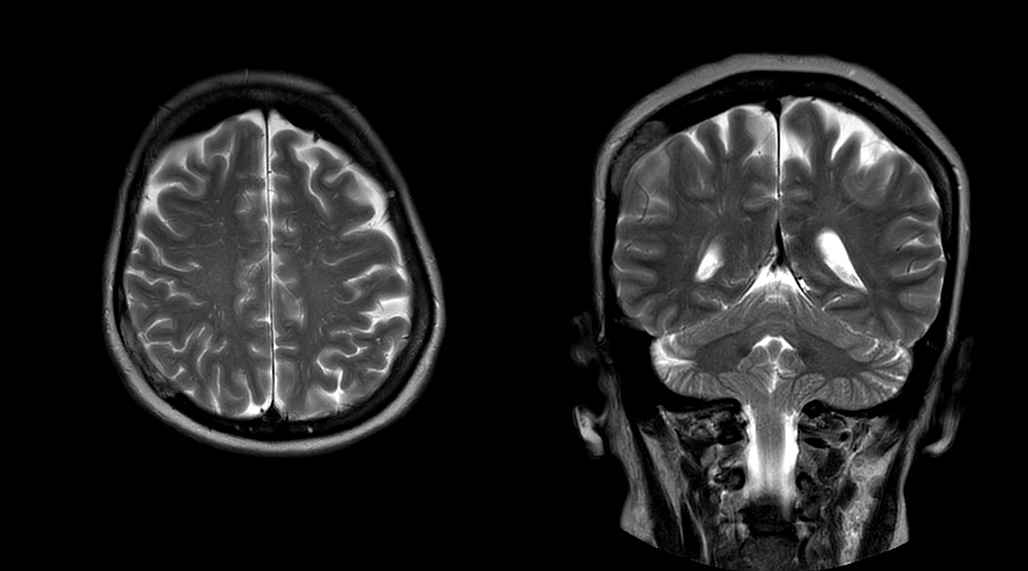

MultiVane XD helps eliminate motion for first-time-right scanning

DMG recognizes MultiVane XD motion compensation is another Philips technique that contributes to image quality and scan efficiency. “We run MultiVane XD for motion-free imaging on almost all our T2-weighted brain scans, just to reduce any repeats we might get. We know our non-contrast brain scans are going to take 20 minutes almost every time,” Mr. Duffy says.

“Using MultiVane XD still allows us to turn on dS SENSE, which significantly cuts scan time compared to what we were doing before,” he adds. “We went from a 2.5 or 3-minute scan to a 1.5-minute scan with no loss in image quality. So, it not only reduces the motion, but also reduces scan time. That gives us a little bit of extra time to speak to our patients and explain the exam a little more.”